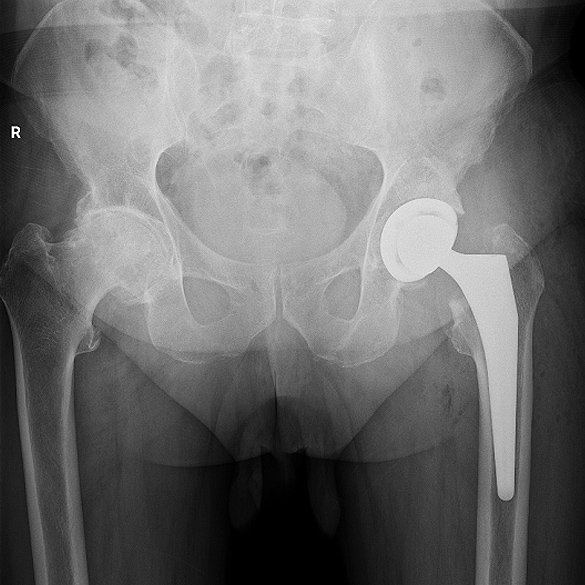

Endoproteza stawu biodrowego

Endoprotezoplastyka stawu biodrowego to skuteczna metoda leczenia choroby zwyrodnieniowej, jałowej martwicy głowy kości udowej, dysplazji oraz innych zmian zwyrodnieniowo-destrukcyjnych stawu jak i złamań szyjki kości udowej. Zabieg polega na usunięciu zniszczonych struktur stawu i zastąpieniu ich odpowiednio dobranym implantem, przywracającym funkcję, ruchomość i komfort życia.